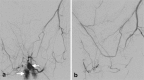

The aim of this study was to identify the frequency of rectosigmoidal involvement in patients with venous malformations (VM) of the lower extremities and to demonstrate multidisciplinary therapeutic options. The medical records and magnetic resonance images (MRI) of patients with VM of the lower extremities, over a six-year period, were reviewed retrospectively in order to determine the occurrence of rectosigmoidal involvement. Vascular interventions, surgical treatments, percutaneous and hybrid (endoscopy-guided angiography) sclerotherapy and procedural complications (according to Clavien-Dindo classification) were also noted. Of the 378 patients with vascular malformation of the lower limbs, 19 patients (5%) had documented venous rectosigmoidal malformation. All of these 19 patients reported episodes of rectal bleeding, while seven patients (36.8%) also had anemia. All patients underwent endoscopy. By endoscopy, seven patients (36.8%) showed discreet changes, and 12 patients (63.2%) showed pronounced signs of submucosal VM with active (47.3%) or previous (15.7%) bleeding. Treatment was performed in all patients with pronounced findings. Six patients underwent endoscopy-guided hybrid sclerotherapy, one patient underwent endoscopic tissue removal, one patient received percutaneous sclerotherapy and one patient received a combination of transvenous embolization and hybrid sclerotherapy. Three patients required open surgery. No complications occurred after conservative treatments; however, one complication was reported after open surgery. None of the treated patients reported further bleeding and anemia at the end of the follow-up period. In this cohort, rectosigmoidal VM occurred in 5% of patients presenting with a high incidence of rectal bleeding. Percutaneous or endoscopy-guided hybrid sclerotherapy appeared to be a safe and effective alternative to surgery.